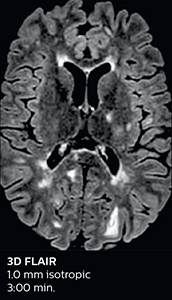

Improving scan time and/or spatial resolution

A two year follow-up scan of a CPA meningioma using both Ingenia 3.0T without CS and Ingenia Elition 3.0T with Compressed SENSE allows for a nice comparison to demonstrate the protocol improvements achieved on the Elition: 3D FLAIR has a shortened scan time, improved SNR and still the same spatial resolution. BrainView (3D T1 TSE) has improved spatial resolution and SNR with shortened scan time. For 3D T2 Drive the spatial resolution has been improved. 3D THRIVE used to have an interpolated 0.8 mm slice thickness, but true thickness at 1.6 mm, so that axial slices displayed a decent quality, but reformats were suboptimal. Compressed SENSE is used on Elition to improve spatial resolution and reduce the non-interpolated slice thickness to allow smoothly reformatted images. Total scan time (adding SmartBrain and an additional b2000 diffusion) was 13:19 on Ingenia, and is now reduced to 10:42 on Ingenia Elition.

Ingenia Elition 3.0T with Compressed SENSE

3D FLAIR 1.0 x 1.0 x 1.0 mm* 2:50 min.

The abbreviated MS protocol for brain is only around 9 minutes, so in case of suspected multiple sclerosis, one or two more advanced sequences may be added, such as PSIR (phase sensitive inversion recovery) or susceptibility-weighted sequences to help us make more confident diagnoses in these inflammatory cases.

“We used to have long examination times for certain types of patients, a few lasting more than 40 minutes,” says Dr. Savatovsky. “What is remarkable, is that now all these examinations are below 30 minutes, which opens up opportunity to add more sequences when needed. It’s really hard to keep a patient for more than 40 minutes in the scanner, but because we have now cut scan times by at least 10 minutes, we can add more sequences without making the exam too long. And this is where the new system helps us make a difference. Examples include our examinations for informing brain tumor classification or giant cell arteritis workup, or for intracranial wall imaging – so in patients where we need several advanced sequences or high resolution sequences.” “We added three additional sequences in our brain neoplasm classification exam: a 3D SWI sequence, APT and ASL on top of 3D morphologic sequences, an isotropic DSC (dynamic susceptibility contrast) and multivoxel spectroscopy. I think that in patients that need a classification for brain mass, for example, we can provide a more detailed and confident diagnosis than before, allowing the clinicians to decide for either a medical workup if no tumor is suspected, or for neurosurgery as soon as possible if a neoplasm is suspected.” “In multiple sclerosis patients, we increasingly include a multishot susceptibility sequence [3] in our routine cases, thanks to the shorter scan times. Our abbreviated MS protocol for brain is around 8 to 9 minutes, so we can ask for one or two additional sequences to visualize the central veins, or to get an additional contrast to better depict posterior fossa lesions. In cases of white matter lesions of unknown significance on FLAIR images, for example when we see high signal hyperintensities in the brain, we can add on more advanced sequences such as PSIR (phase sensitive inversion recovery) or susceptibility-weighted sequences to help us in distinguishing between MS and nonspecific or vascular abnormalities in these inflammatory cases.”